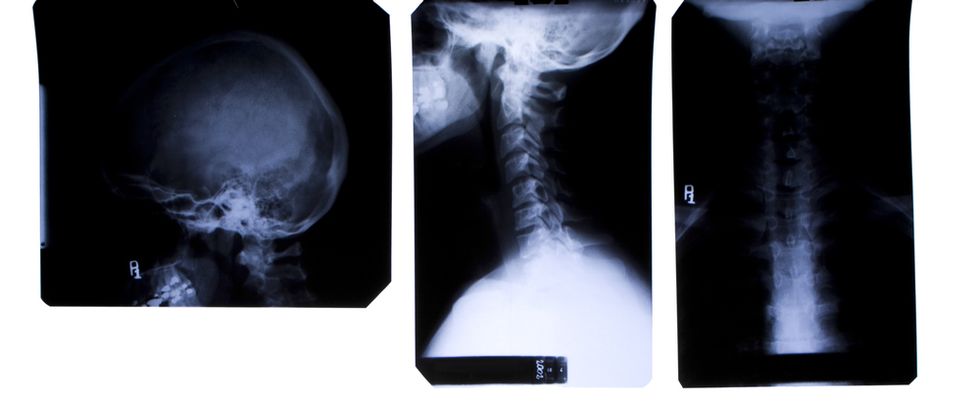

According to the Austrian Times, the patient was brought to the hospital in Krasnoyarsk, Russia, complaining of pain in his throat and difficulty breathing. He was given an X-ray, which revealed an object stretching his esophagus from its normal diameter of about 2-3 centimeters to four or five times that size.